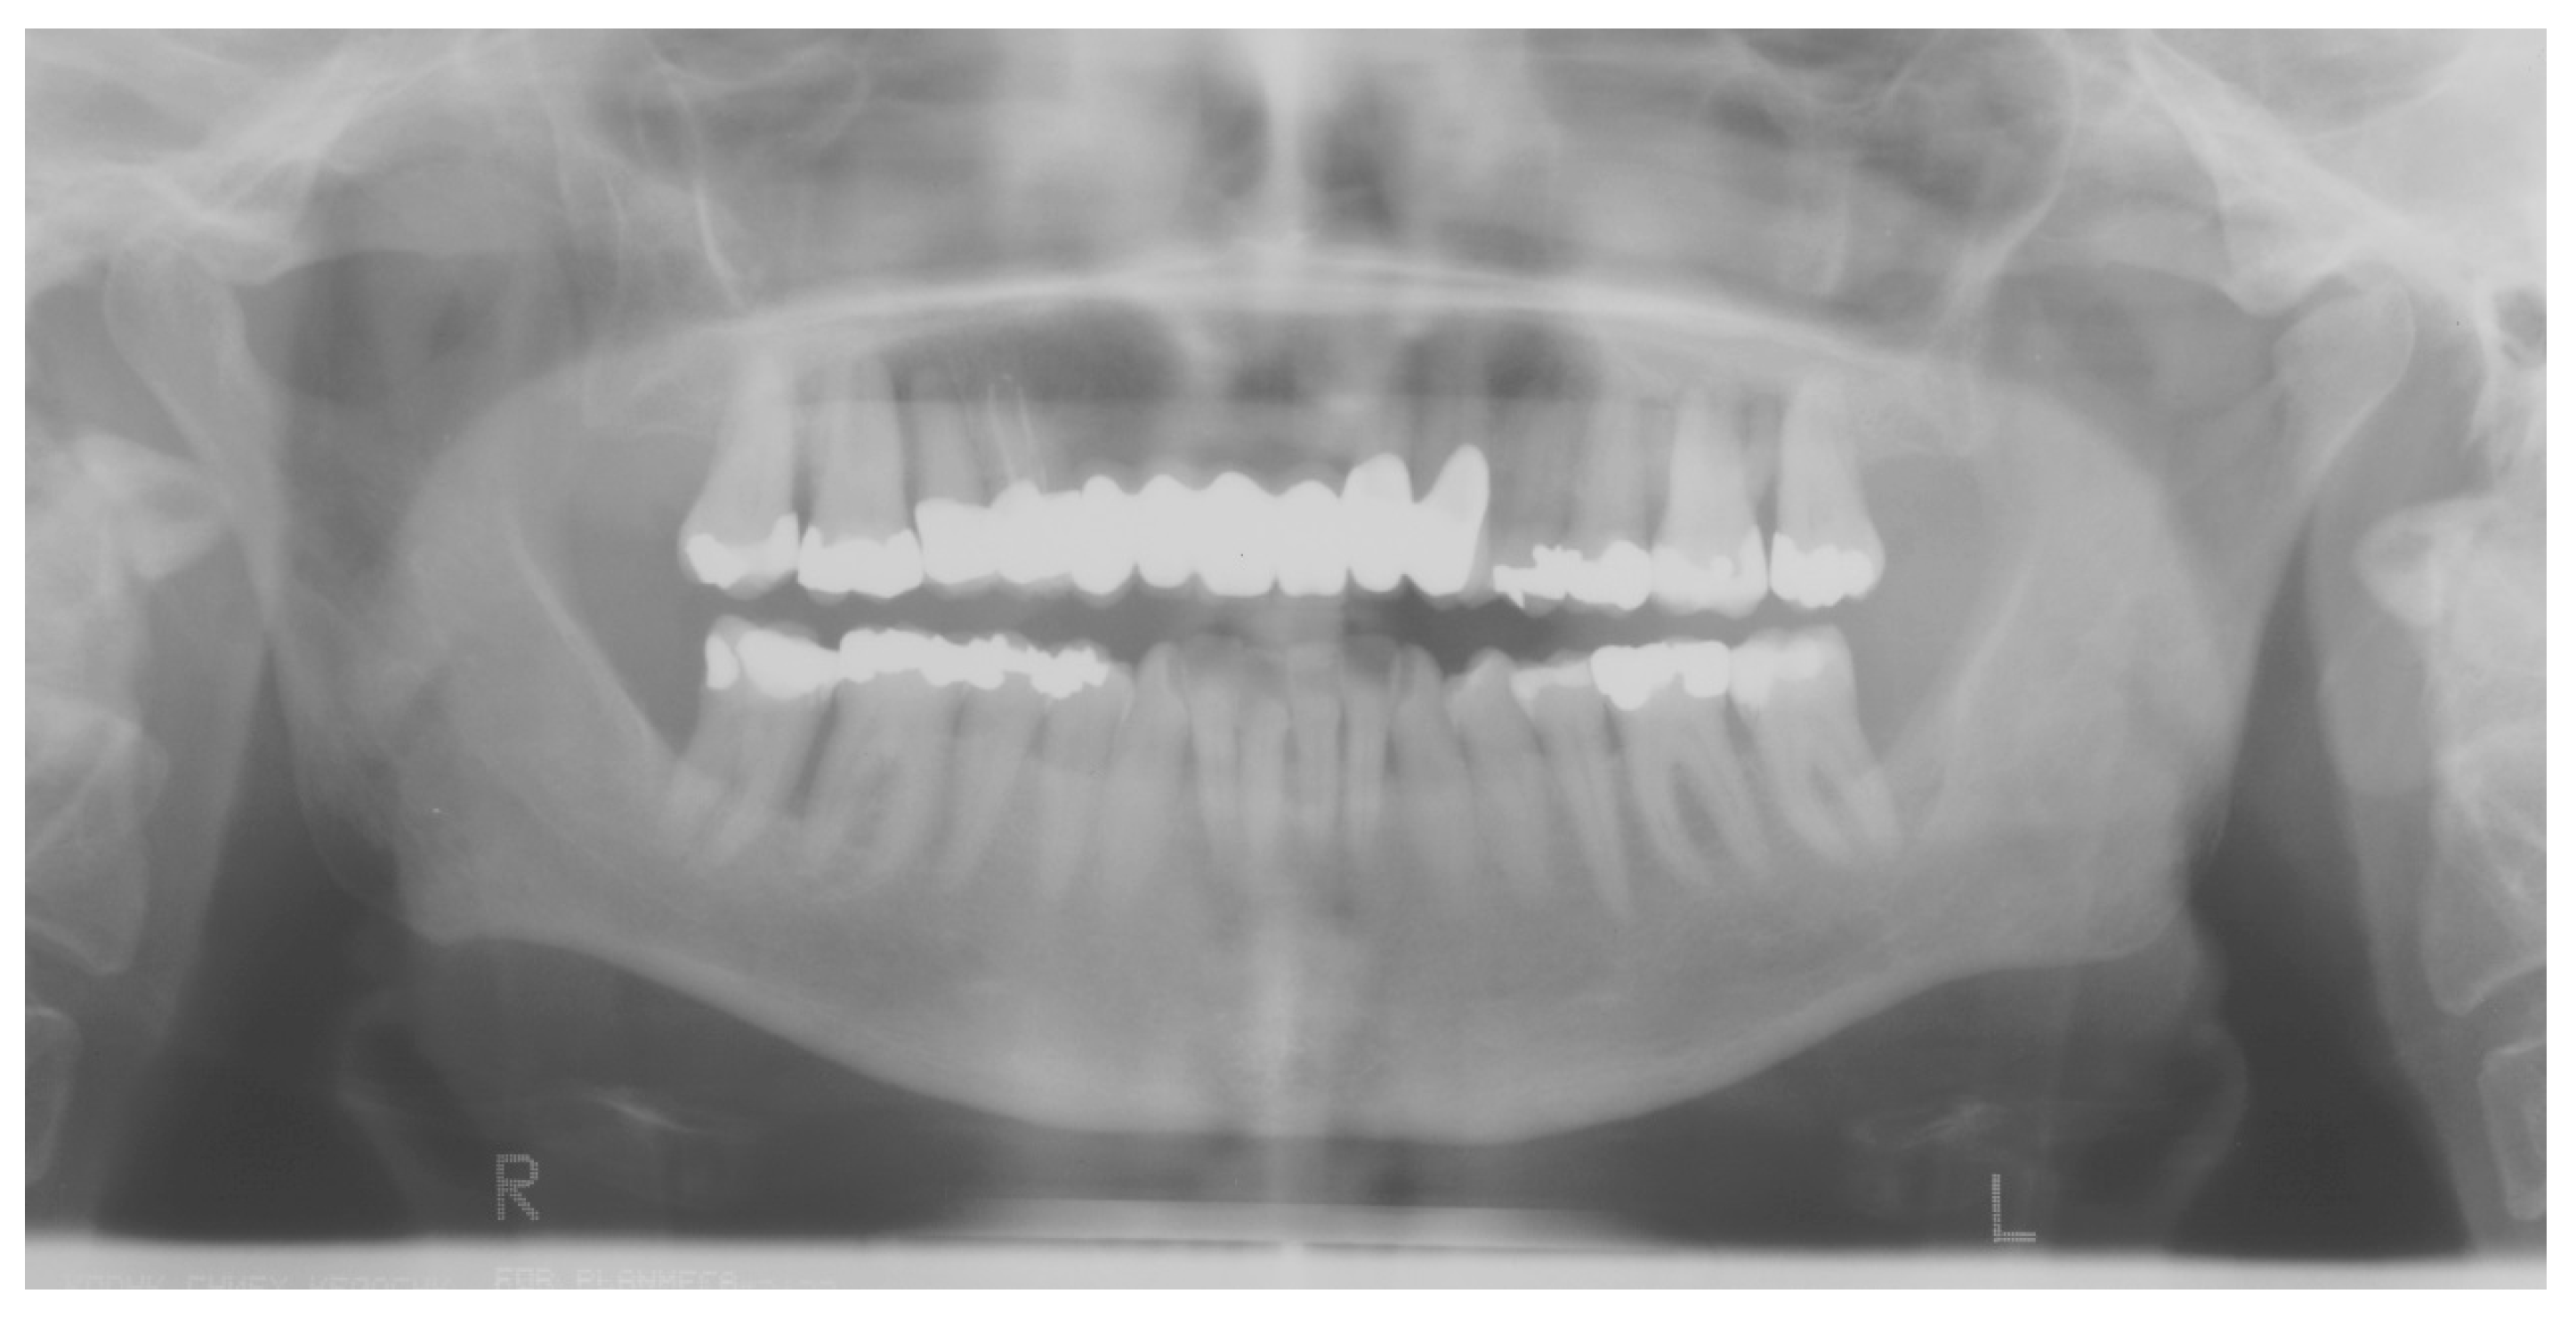

| Papillon–Lefèvre syndrome/Keratosis palmoplantar-periodontopathy syndrome Q82.8 | periodontitis | exact pathomechanism unknown [72] | CTSC, 11q14.2 [41,94] | systemic diseases and conditions that affect the periodontal attachment apparatus: diseases associated with immunologic disorders |